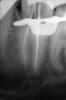

Денис481 Опубликовано 6 июня, 2013 Поделиться Опубликовано 6 июня, 2013 Пациентка пульпит 37 анестезия по пальцу в ухе))))кстати чудодейственная,затем вскрыл сразу 2 канала нашел передний и задний щечный,дальше рою хоть убей нету больше,уже и глубоко зашел нету ,ну решил 2 запечатать и у вас узнать не может же быть их 2, явно где то сидит,хотя по снимкам не видно мне, прошел мту до 20 передний до 25 задний и латералкой закрыл учитывая предыдущие замечания Ссылка на комментарий

Kivilgar Опубликовано 6 июня, 2013 Поделиться Опубликовано 6 июня, 2013 Медиальный не плотно как-то запакован. И до 20 маловато. 1 Ссылка на комментарий

Каплан Опубликовано 6 июня, 2013 Поделиться Опубликовано 6 июня, 2013 и даже 25 мало. медиальный второй может быть внутри устье. Ссылка на комментарий

Мартовский Опубликовано 6 июня, 2013 Поделиться Опубликовано 6 июня, 2013 Пациентка пульпит 37 анестезия по пальцу в ухе))))кстати чудодейственная,затем вскрыл сразу 2 канала нашел передний и задний щечный,дальше рою хоть убей нету больше,уже и глубоко зашел нету ,ну решил 2 запечатать и у вас узнать не может же быть их 2, явно где то сидит,хотя по снимкам не видно мне, прошел мту до 20 передний до 25 задний и латералкой закрыл учитывая предыдущие замечанияЧаще всего ненайденный третий канал в нижних семерках означает необработанный С-шейп. 2 Ссылка на комментарий

METT Опубликовано 8 июня, 2013 Поделиться Опубликовано 8 июня, 2013 Вообщем дул поливал прыгал с бубном,исполнял ламбаду,не реагирует зуб совсем,решил завязывать с ним пломба из градиа и давай до свиданиямне кажется, там еще чуть-чуть и бифуркация станет...нецелой... Ссылка на комментарий